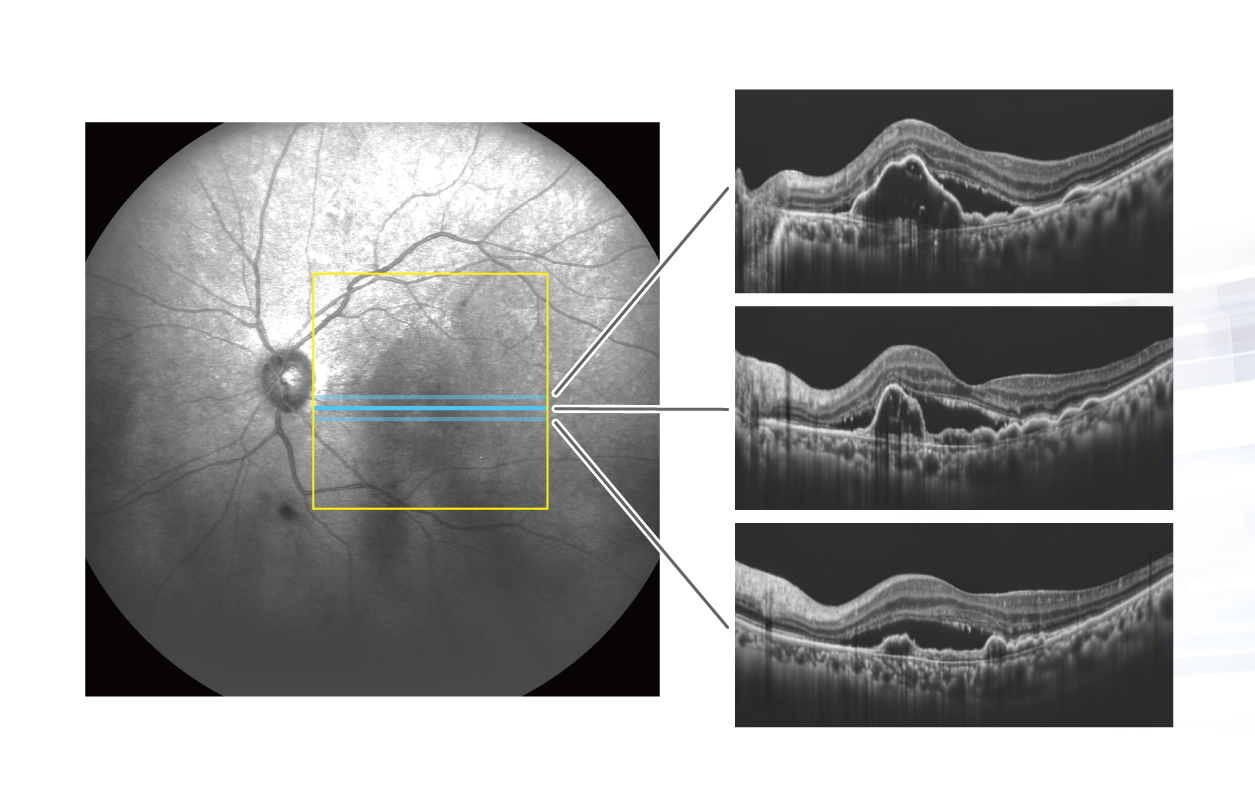

Glauvas 網膜マップ 15×12mm 水平B-scan+GCC+RNFL

ひとつの検査結果でさまざまな網膜疾患の診断に必要な画像や解析結果を表示することができます。